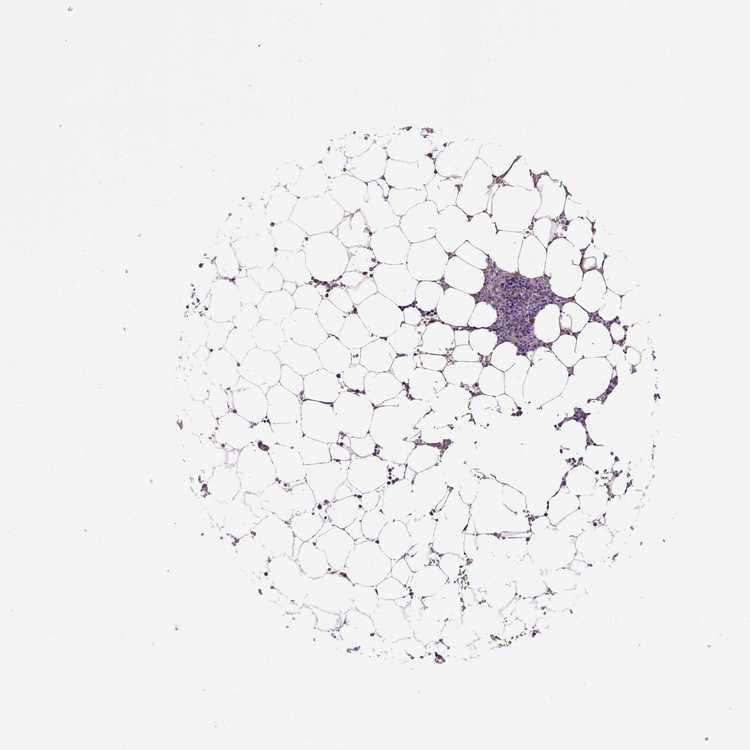

TISSUE PRIMARY DATA BONE MARROW Show tissue menu

BONE MARROW - Antibody stainingi

Antibody staining in the annotated cell types in the current human tissue is reported as not detected, low, medium, or high, based on conventional immunohistochemistry profiling in selected tissues. This score is based on the combination of the staining intensity and fraction of stained cells.

Each image is clickable and will lead to virtual microscopy that enables deeper exploration of all samples and also displays staining intensity scores, fraction scores and subcellular localization as well as patient and tissue information for each sample.

Antibody HPA038585

Hematopoietic cells Low